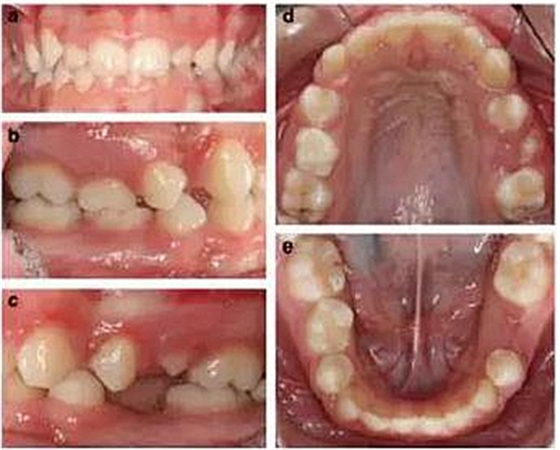

患者 女 13歲

患者面型對稱,面上下比例對稱,輕度凸面型,鼻唇角正常;

輕度牙齦炎,口腔衛(wèi)生一般,無齲??;

右側II類磨牙關系和尖牙關系,左側I類磨牙關系和尖牙關系;

深覆合,前牙輕度不齊,下中線右偏2mm;

上下頜右側第二乳磨牙存,其余乳磨牙已脫落;